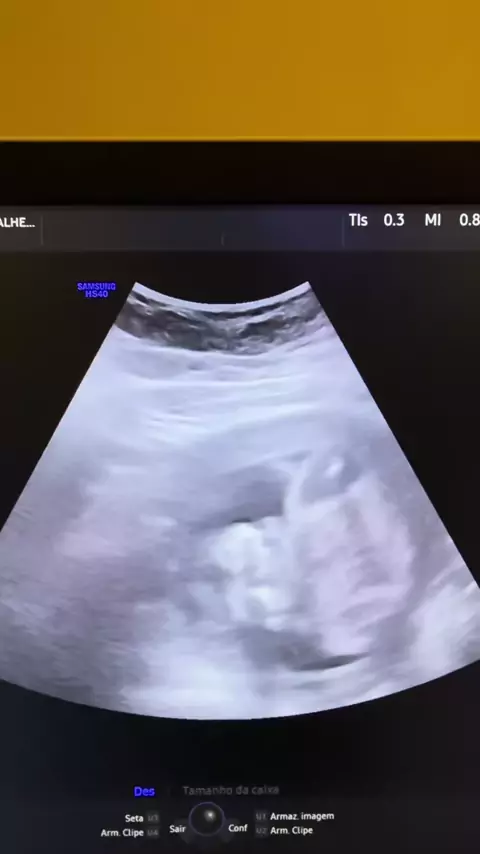

ELA VEIO PREPARADA PARA PERDER O ÚTERO. E DESCOBRIU QUE ESTAVA GERANDO UMA VIDA. Hoje eu vivi uma das cenas mais marcantes da minha carreira. Ela entrou na sala com medo. Disseram a ela que tinha miomas. Disseram que tinha endometriose. Disseram que precisaria tirar o útero. Que era urgente. Ela estava pronta para uma cirurgia. Estava pronta para se despedir do sonho de ser mãe. Eu comecei o exame como sempre faço: pelo abdômen. E ali… o silêncio da sala mudou. Um coração batendo forte. Um corp...